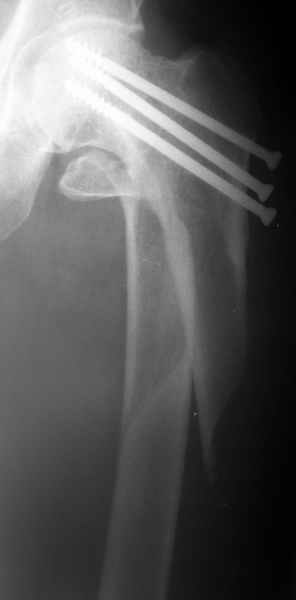

Еще один перелом "около фиксатора" |

Женшина 69 лет оперирована у нас 2 года назад по поводу перелома шейки. Ходила дома без дополнительной опоры, на улице - с тростью.

Сегодня утром села мимо табуретки. Поскольку наша бывшая пациентка, сегодня же из области родственники привезли к нам. Картинка в приложении. Какие будут предложения по тактике?